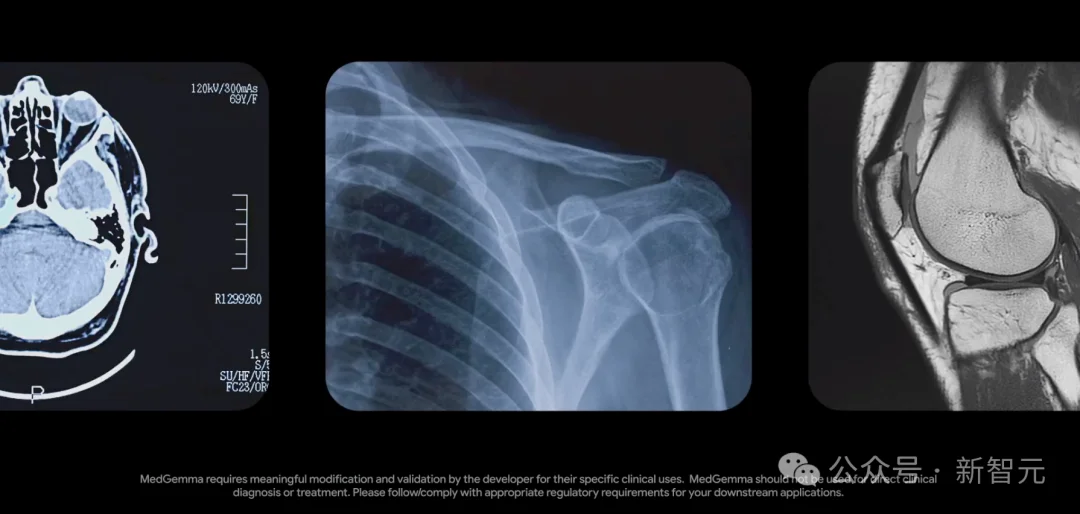

5月,谷歌DeepMind曾开源了强大的医疗模型MedGemma,在多模态医学文本和图像理解上表现优异。

三、多模态深度赋能临床

影像和文本,从来不是两条独立的信息链。

山海·知医大模型5.0升级后,兼具「看懂影像」和「读懂文本」的双重能力。

它不仅能精准识别X光、CT、MRI等影像中病灶,还能将影像特征映射到医学语义空间中。

也就是说,它可以实现影像特征与临床描述的跨模态语义对齐及联合推理。

这就好比为医生配备了「图文协同」智能助手,大幅提升诊断的精准性与效率。